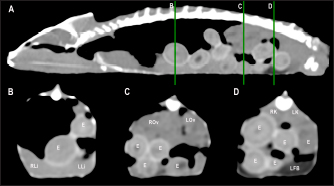

Fig. 8. Sagittal precontrast CT image displayed in soft tissue window (A) and selected corresponding transverse images represented as green line section, displayed in soft tissue window at the level of the liver (B), ovaries (C), and kidneys/fat bodies (D) in a female panther chameleon (F. pardalis). E, eggs; RLi, right liver lobe; LLi, left liver lobe; ROv, right ovary; LOv, left ovary; RK, right kidney; LK, left kidney; LFB, left fat body.

The ovaries were identified cranial to the kidneys in 4 of 10 (40%) female veiled chameleons. They could be visualized as a cluster of multiple circular structures, the ovarian follicles, (with a grape-like appearance) with soft tissue attenuation in 2 of 10 (20%). Mild diffuse enhancement of these structures could be observed after contrast administration (Figs. 7 and 8). The diameter of the follicles ranged from 0.19 to 0.40 cm. When eggs were seen (2/10, 20%), they appeared as ovoid structures with alternating hyper and hypoattenuating layers (Fig. 8). The center of the egg had fluid attenuation and the peripheral line with mineral attenuation was the shell. The size of the eggs ranged from 0.56 to 0.80 cm in width and from 0.93 to 1.70 cm in length in veiled chameleons. The precontrast attenuation range of ovarian follicles was 25.5–39 HU in female veiled chameleons depending on the stage of follicle and egg development. The postcontrast attenuation range was 31.10–44.25 HU.

The liver was observed as a structure with low soft tissue attenuating values and it was incompletely bilobed. The right lobe was larger than the left one (Figs. 5, 6, and 8). After contrast administration, the liver parenchyma showed homogeneous contrast enhancement. The hepatic veins and CVC were better defined from the adjacent parenchyma as a hyperattenuating tubular structure. The liver measurements are included in Table 1 and pre and postcontrast attenuation values are included in Table 2.

Kidneys

Fat bodies